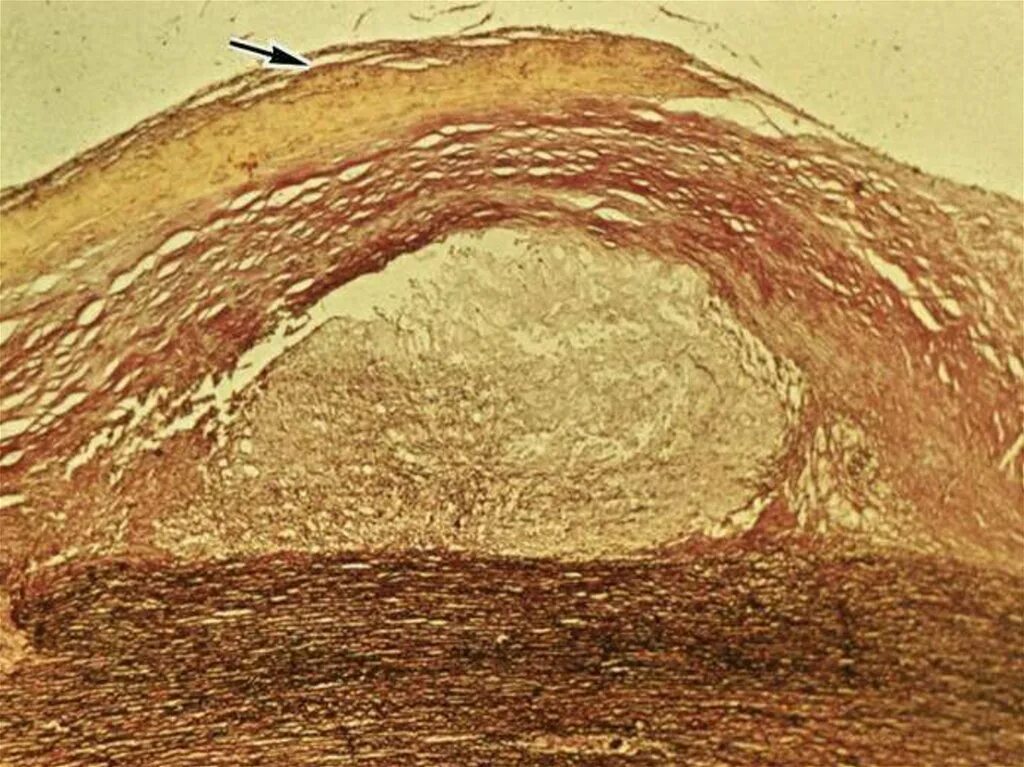

Атеросклероз аорты препарат